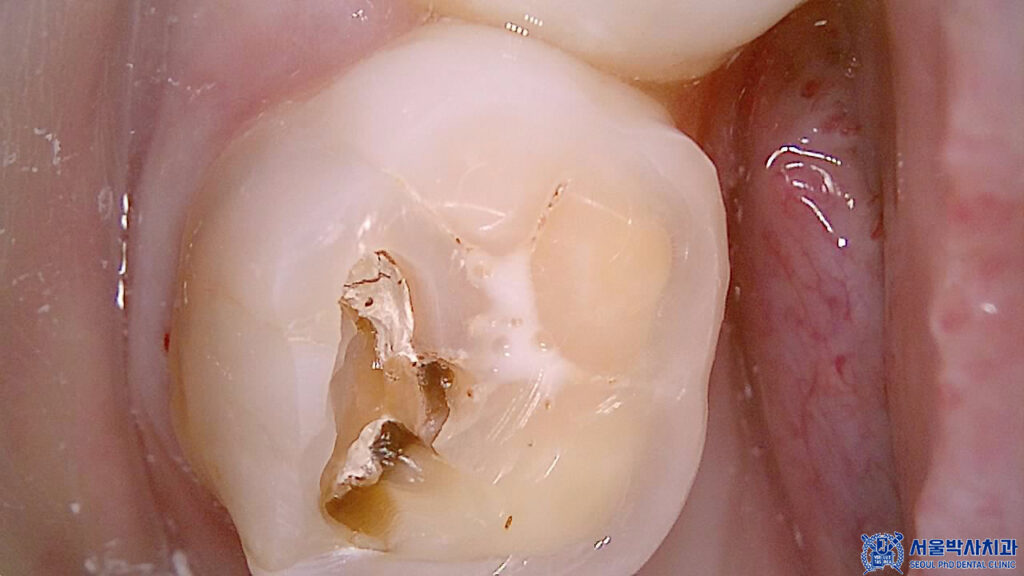

먼저 충치가 매우 깊었던

왼쪽 위 큰 어금니는

충치로 인해 치아가 파절되어 있는

상황이었습니다.

또한 씹는면 주변으로

치석이 쌓여있는 것으로 보아

관리가 잘 안되고 있는것으로

볼 수 있었습니다.